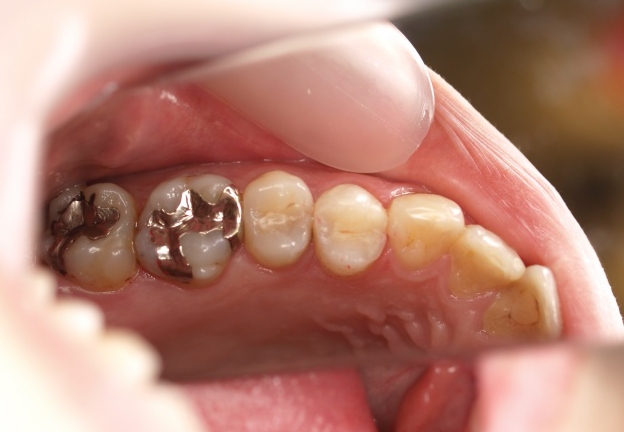

ハイブリッドセラミックス修復

担当歯科医師:丸林浩太郎

2013年3月2日千葉市中央区 S.K様 左下6番 ハイブリッドセラミックインレー修復